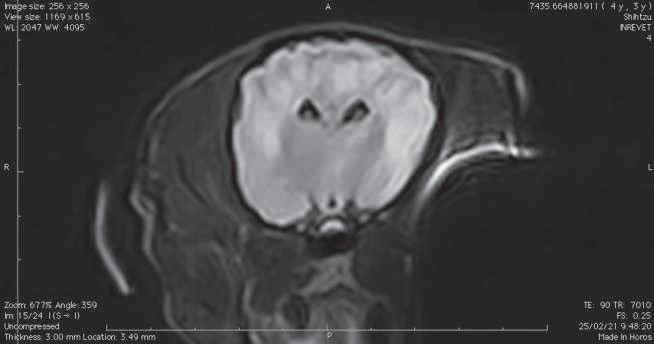

Figura 1. (A y C) Imágenes ponderadas en T2W. (B y D) FLAIR con lesiones hiperintensas en múltiples regiones encefálicas asociados a focos de edema con mayor evidencia en núcleos basales y tálamo (A, B) y lóbulos parietales y temporales (C y D).

Figura 2. Imágenes ponderadas en T2W (A, C) y FLAIR (B, D) en las cuales se aprecia una disminución en las lesiones hiperintensas descritas en la figura 1.

Conbasealosresultadosderesonancia magnética (Figura 1), raza y hallazgos neurológicos los pacientes fueron diagnosticados con enfermedad inflamatoria cerebral (Meningoencefalitis de origen desconocido) e iniciaron con una terapia basadaenStee2020,10 conlacombinación decitarabina(Cytosar-U®Pfizer500mg) a dosis de 100/m2 y prednisona a dosis de 1 mg/kg iniciales por 4 semanas (dosis reducción a 36 semanas), para posteriormente evaluar la evolución clínica del paciente y por imagen con las mismas indicaciones de resonancia previamente descritas.

En el presente estudio 5 de 6 pacientes mostraronunamejoracínicasignificativa, enunpaciente(Shih-tzu)elcualingresóen estatus epiléptico no presentó más crisis convulsivas ni se han reportado hasta el momento, el estado mental de los 6 pacientes mejoró de forma significativa, sólounpaciente(Yorkshire)conimágenes por resonancia magnética con herniación subfalcina continuó con giros, los déficits propioceptivos continuaron en 2 de 6 pacientes (Cuadro 3). En las imágenes por resonancia magnética posterior a las 4 semanas iniciado el tratamiento se vio unadisminucióndeledemareportadoque va desde el 85% hasta 50% (Figura 2).

El propósito del presente estudio fue determinar la relación entre la respuesta clínica y la evaluación de las imágenes por resonancia magnética en estudios seriados usando un protocolo de tratamiento basado zen las regiones con hiperintensidad enT2Wfue notoria en la mayoríadeloscasosdescritos.Sepresentó una predilección en hembras (4 de 6) como varios estudios han reportado.1,7,11 Dos casos se presentaron con convulsiones agudas sintomáticas, uno de ellos en estatus epiléptico, Kaczmarska, et al., reportaron una prevalencia del 50% de convulsiones,5 en algunos otros reportes varía del 23% al 37.5%.12,13 Se ha informado que la RM tiene una sensibilidad

del 94.4% y una especificidad del 95.5% para detectar una anomalía cerebral, con un rendimiento similarmente alto para clasificar enfermedades neoplásicas e inflamatorias,14 aunque actualmente no hay información disponible sobre el uso deresonanciamagnéticaparadiferenciar entrecasosconfirmadoshistopatológicamente de MEG, MEN, LEN.